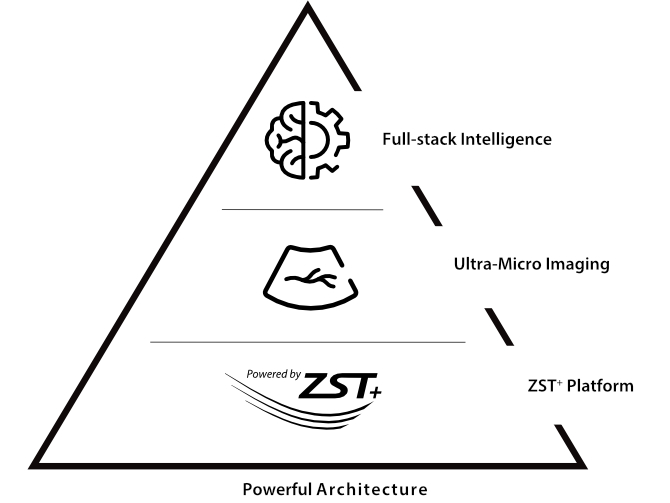

Gra?as Ć revolucionĆ”ria plataforma ZST+, o Nuewa R9 Ć© equipado com tecnologias avan?adas e inovadoras para enfrentar os desafios diagnĆ³sticos na saĆŗde da mulher. Tecnologias revolucionĆ”rias, como a angiografia ultramicroscĆ³pica (UMA), ajudam vocĆŖ a explorar mais microdetalhes e a realidade escondida. Projetado com a inestimĆ”vel sabedoria de especialistas, ele oferece informa??es completas de forma inovadora, que v?o alĆ©m de suas expectativas para diagnĆ³stico com mais confian?a, padroniza??o e eficiĆŖncia frente aos diferentes desafios em ambientes hospitalares exigentes e sobrecarregados.

Explore mais detalhes e realidade escondida

UMA (angiografia ultramicroscĆ³pica)

A tecnologia inovadora elimina as limita??es das tradicionais imagens com Doppler. Com resolu??o espacial e sensibilidade de fluxo ultra-altas, permite a detec??o de perfus?es de fluxos muito sutis e lentos, ampliando assim a aplica??o clĆnica da avalia??o qualitativa e quantitativa do ultrassom no cĆ©rebro fetal, rins, placentas, endomĆ©trios, ovĆ”rios etc.